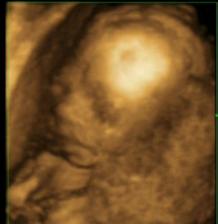

V bříšku

25týden,holčičkA